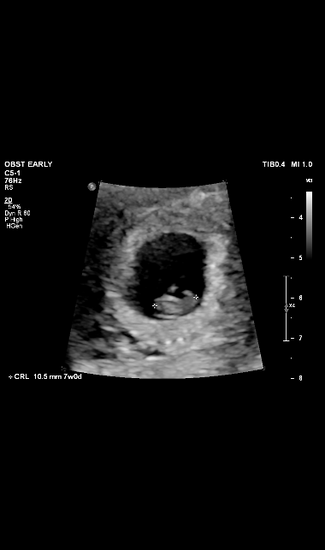

When we returned home, we had our first ultrasound at 7 weeks at Beautiful Beginnings. I braced for the worst, but there on the screen was a healthy little baby with a strong heartbeat. She looked just like a jellybean, and that’s been her nickname ever since. Sitting in the car afterwards, I told Ethan straight: “I can’t not have this baby. If you don’t want this, I’ll give the ring back and do it alone.” It was blunt, but it was the truth. After some time, he agreed—we’d figure it out together.